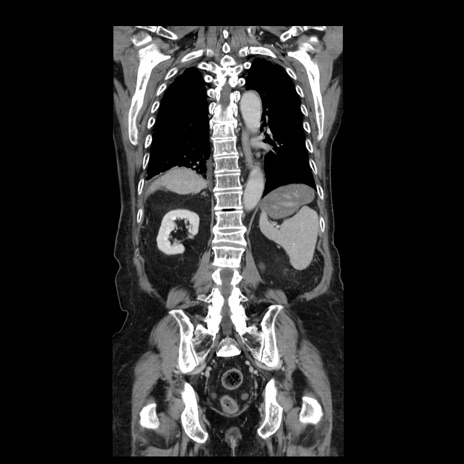

症例21(冠状断像)

【症例】70歳代男性

【主訴】腹痛

【現病歴】肝硬変・肝細胞癌にてかかりつけの方。約9時間前に食後より腹痛出現。症状が徐々に増悪し、嘔吐出現したため来院。

【既往歴】肝硬変、肝細胞癌(RFA、TACE後)

【身体所見】意識清明、表情苦悶様、BT 36℃、BP 129/78mmHg、P 88bpm、SpO2 97%(RA)、右上腹部から心窩部にかけて圧痛あり、反跳痛なし、筋性防御あり。

【データ】WBC 5800、CRP 0.16